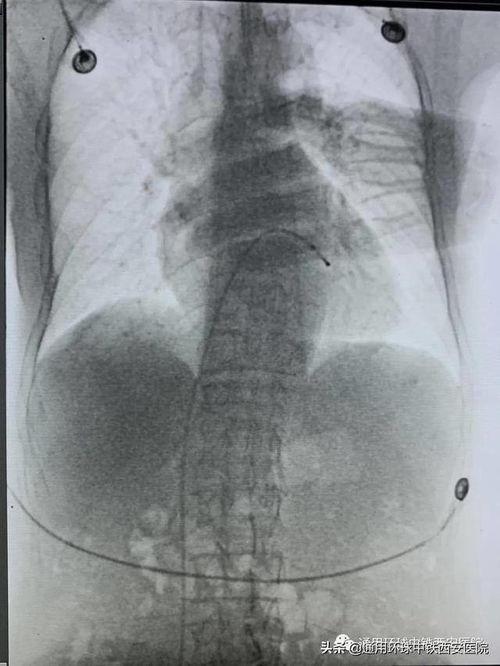

3. 连接过程:视频还展示了起搏器与心脏连接的过程。你可以看到,医生将导线从起搏器中引出,并将其连接到心脏的特定位置。这个连接过程需要非常精确,因为只有这样才能保证起搏器能够正常工作。